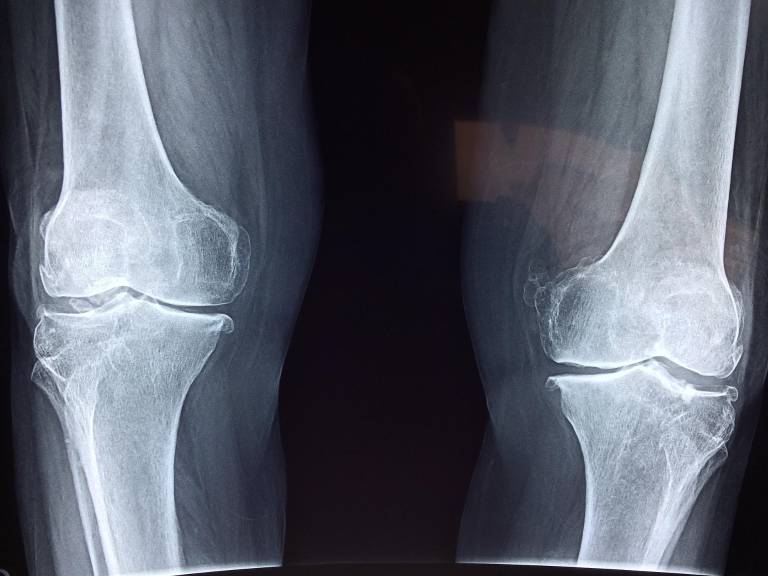

La operación, cuyo origen se remonta a descubrimientos científicos que hicieron con relación a la recuperación de soldados amputados en la Segunda Guerra Mundial, involucra la fractura de dos huesos y un largo proceso de recuperación.

Para concretarla, los doctores fracturan deliberadamente el fémur de cada pierna en dos, y en cada lado colocan un pequeño objeto magnético, los cuales extienden el hueso progresivamente durante su proceso de recuperación natural.

La razón por la que el hueso se alarga como consecuencia de la separación se debe a la "osteogénesis", como está denominado el crecimiento del tejido óseo capaz de rellenar pequeñas separaciones.